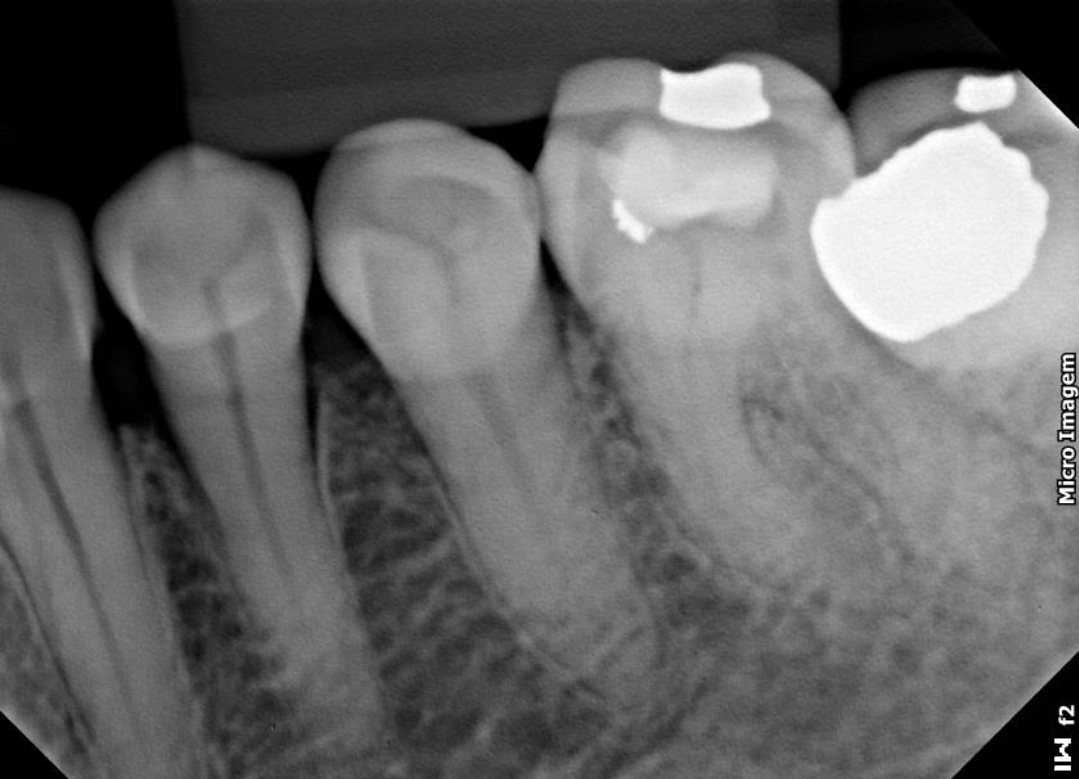

No artigo a seguir vamos mostrar o caso de um molar inferior com cinco canais. Dentre eles, o canal mésio-medial – localizado entre o mésio-vestibular e o mésio-lingual – e que está presente entre 1 e 15% dos casos.

A paciente foi encaminhada já com o acesso realizado no dente 36, após o diagnóstico de pulpite aguda irreversível. Após a anestesia, isolamento do campo operatório e remoção da restauração provisória, foram encontrados cinco canais com auxílio da microscopia. Entre eles, o canal mésio-medial, na raíz mesial, e situado entre o canal mésio-vestibular e o mésio-lingual.

A obturação foi realizada com a técnica do cone único com cimento AH Plus. O selamento da cavidade de acesso foi feito em resina composta e o paciente encaminhado para o protesista.

Neste caso, usamos as limas Reciproc Blue 25.08, ou seja, um diâmetro inicial de 25mm com uma conicidade ou taper 08mm. Após um glide path realizado com instrumento fino (10.02), percorremos e exploramos o canal radicular até o forame apical com uso dos localizadores apicais eletrônicos.

Neste caso, nós usamos a solução irrigadora soro fisiológico e clorexidina. Antes da obturação, uma agitação com ultrassom da solução EDTA e a técnica do cone único com cimento AH Plus.